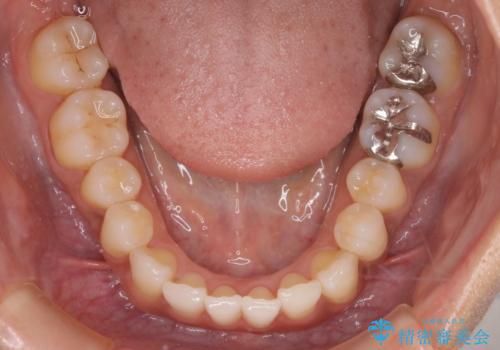

【インビザライン】前歯をきれいな歯並びにしたい

- 前歯の叢生を主訴に来院されました。このケースは抜歯をせずにIPRにてスペースを確保し、並べる計画をたてました。

きちんと使用時間を守って使用していただいたことで短い期間で治療が終了しました。